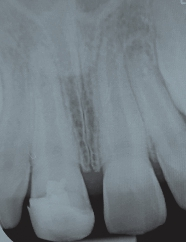

Die aufgrund einer infizierten oder nekrotischen Pulpa notwendige endodontische Behandlung, beispielsweise nach einem dentalen Trauma, kann durch ein weit offenes Foramen apikale bei einem noch im Wachstum befindlichen Zahn deutlich erschwert sein. Die noch dünnen und grazilen Dentinwände sowie das nicht abgeschlossene Längenwachstum führen zu einem ungünstigen Kronen-Wurzel-Verhältnis und zu einer erhöhten Frakturgefahr des betroffenen Zahnes (Abb. 3). Durch die bisherige Therapie, der Apexifikation, und der damit geschaffenen apikalen Barriere konnten zwar im Anschluss die notwendige endodontische Behandlung sowie Wurzelfüllung durchgeführt werden, das Frakturrisiko verringert sich jedoch nur minimal. Das Ziel ist es also, eine Therapiemöglichkeit zu schaffen, die sowohl ein Längen- und Dickenwachstum der Wurzel fördert als auch die Bildung eines physiologischen Apex induziert und damit die Prognose des Zahnes langfristig erhöht. Die regenerative Endodontie kann die weiterführende Entwicklung des Zahnes ermöglichen (Abb. 4). Voraussetzung für diese erfolgreiche Durchführung ist eine ausreichende Desinfektion, ein offenes Foramen apikale und ein nicht aufbereiteter Wurzelkanal.